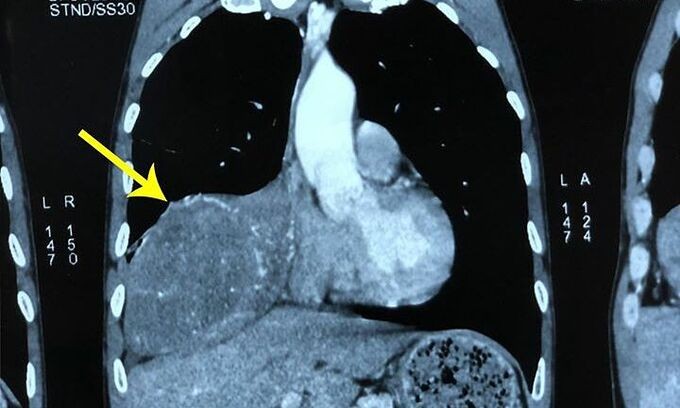

Xẹp phổi bởi khối u trong lồng ngực

Bệnh nhân cho biết, cách đây khoảng 2 tháng, ông thấy đau nhói bên ngực phải mỗi lần nằm nghiêng và trở mình. Tình trạng đau tức ngày càng tăng gây mệt mỏi, ông đi khám và được chẩn đoán u phổi phải. Kết quả chụp cộng hưởng từ và cắt lớp vi tính cho thấy phổi phải có khối u kích thước 11x18 cm gây xẹp phổi.

Kết quả giải phẫu bệnh cho thấy khối u là loại u xơ đơn độc màng phổi (Solitary Fibrous Tumors). U xơ đơn độc màng phổi là một dạng tổn thương ít gặp thường xuất phát từ lớp tế bào cận trung biểu mô, chiếm chưa đến 5% các khối u ở màng phổi. Khối u thường không gây triệu chứng lâm sàng trong giai đoạn sớm và chỉ phát hiện tình cờ khi chụp phim X-quang phổi định kỳ.